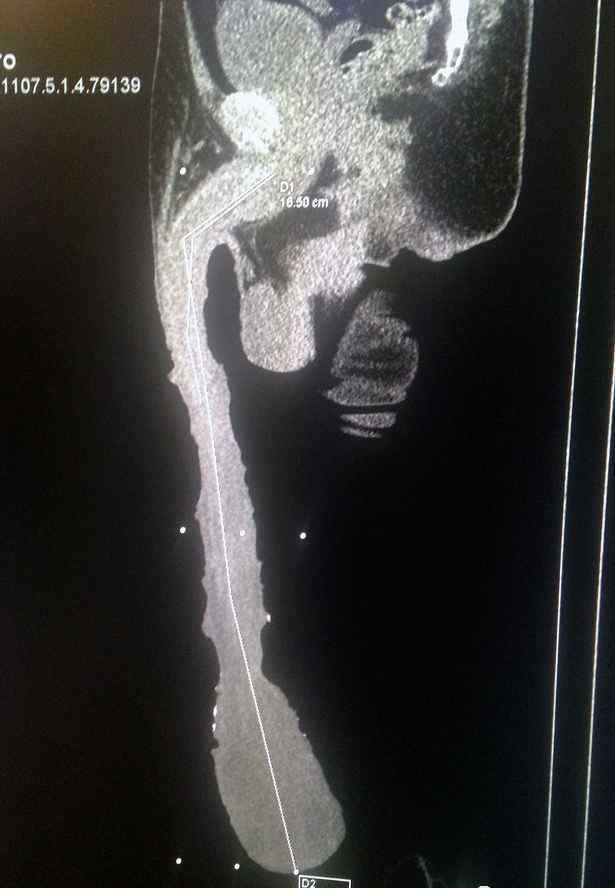

他认为这一切的根源都在大脑。根据扫描结果,卡夫雷拉在大脑的右颞叶有一些病变...

拍片检查结果显示,卡夫雷拉的《丁丁历险记》准确长度为48.21厘米...

晴天-七里香:今天看到这个新闻。你知道事实是什么吗?他自称的41cm其实只有16.5cm,其余都是包皮

彭伯聪一:看拍的x光片,其实丁丁不长,只是包皮太长,里面的脂肪堆积。